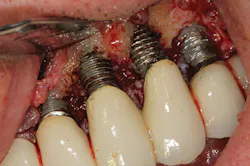

Peri-implantitis has been defined as an inflammatory process that affects the tissues around an osseointegrated implant in function and, like periodontitis, results in loss of supporting bone6 (Figs. 3 and 3a). The prevalence of peri-implantitis has been shown in some studies to range from 11% to as high as 47% of implant sites analyzed.(16) Most literature reviews agree that once bone loss has occurred around an implant, nonsurgical therapy is not as effective as surgical treatment.(17) Surgical intervention by the dentist or specialist includes raising a full thickness flap around the affected dental implant in order to completely expose the dental implant surface (Fig. 4). Mechanical debridement with hand and high-speed instrumentation as well as irrigation with various medicaments is advocated in order to detoxify the implant surface and alleviate bacterial contamination. After decontamination, the flap can be apically or coronally positioned. In addition, various regenerative technologies, including bone and soft-tissue grafts, growth factors, and barrier membranes have been used to rebuild lost tissue support around the dental implant (Figs. 5 and 5a). Different methods of guided bone regeneration around implants affected with peri-implantitis were demonstrated, and the results have been shown to be stable for a follow-up period of up to seven years.(18) That being said, no gold standard of peri-implant disease has been documented and "available evidence does not allow specific recommendations for the therapy of peri-implantitis."(19)